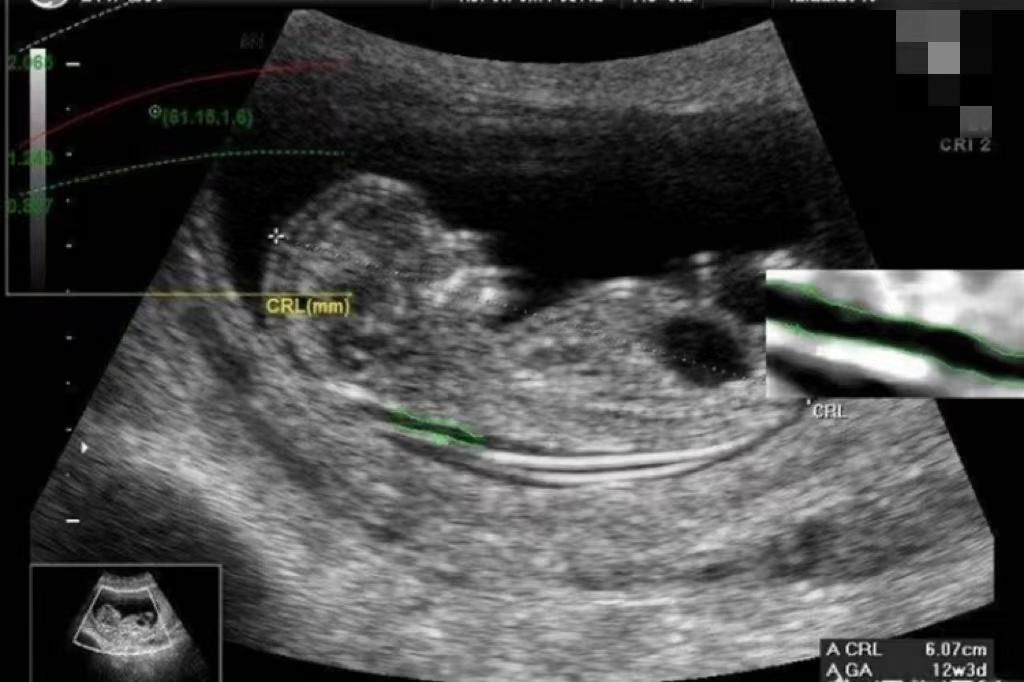

1、胎儿颈项透明层厚度:NT检查主要是通过B超测量胎儿颈部皮肤层到皮下软组织间的无回声区,即颈项透明层的厚度。这个厚度可以反映胎儿颈后部皮下组织内液体积聚的情况,是评估胎儿是否存在发育异常的重要指标。

NT检查的最佳时间是在妊娠11至13周+6天之间,在这个时间段内,胎儿颈部淋巴管与颈静脉窦相通,少量淋巴液积聚在颈部,形成暂时性的颈部透明带,这为NT检查提供了良好的观察条件。

NT检查结果的正常值范围与检查时的孕周有关,一般来说,如果检查时的孕周在11至12周之间,NT检查结果的正常值应小于2.5mm。如果检查时的孕周大于12周但不超过13周+6天,NT检查结果的正常值应小于3.0mm。需要注意的是,不同医院或机构可能采用的标准略有不同。